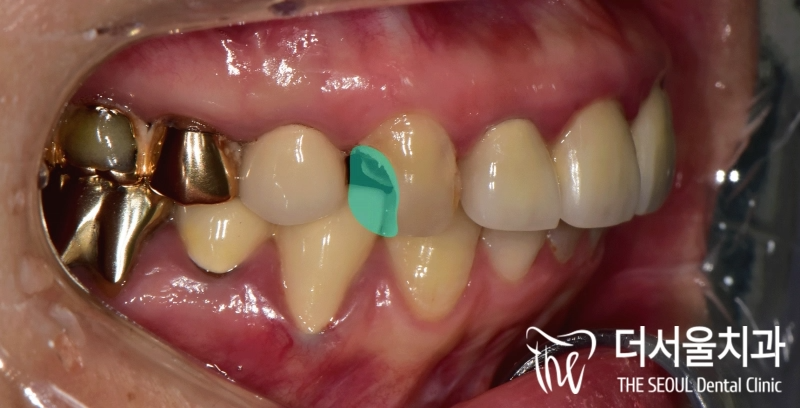

안녕하십니까, 박현준 원장입니다. 치아가 파절 된 범위에 따라서 발치를 해야 되느냐 또는 보존치료를 하느냐 결정이 됩니다. 여기서 환자의